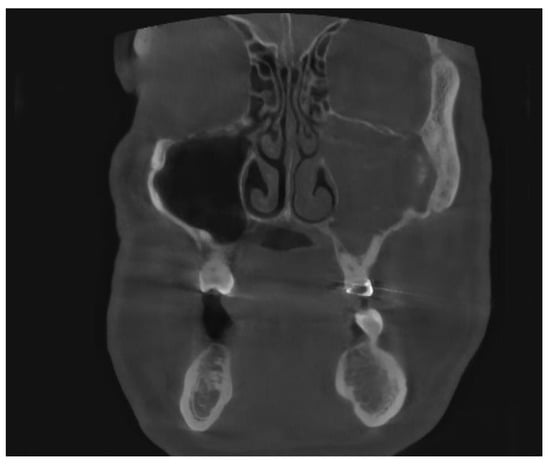

Figure 7. CBCT image of bilateral maxillary sinusitis caused by blade implants; chronic OAF (oroantral fistula) next to the implants. ((A): coronal, (B): sagittal, (C): axial view).